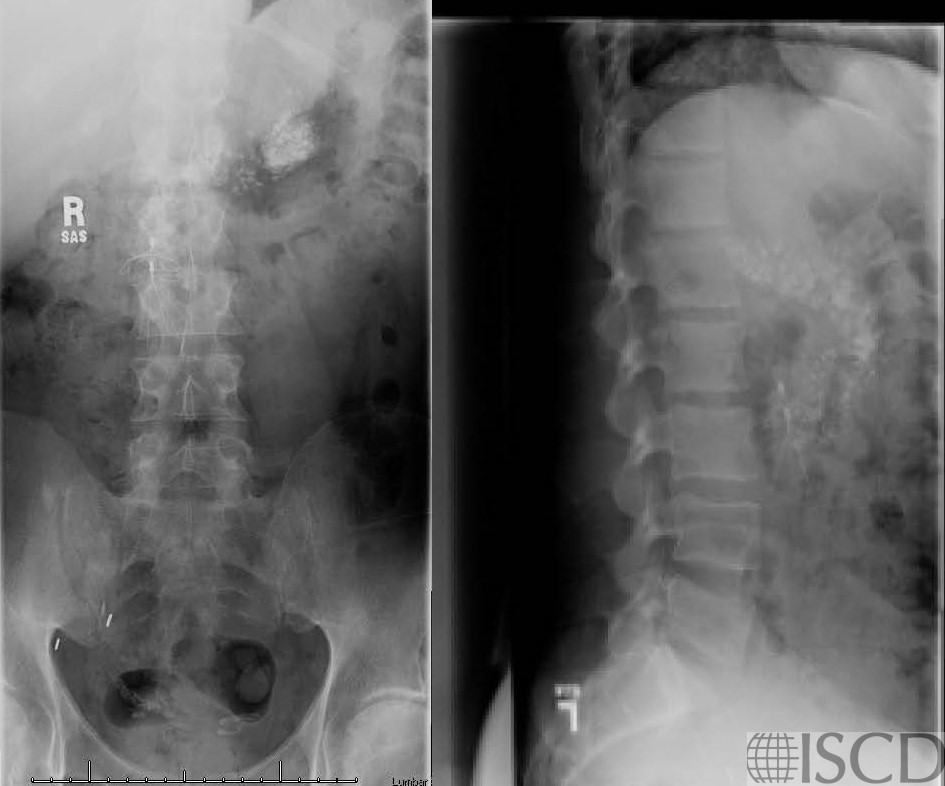

The accompanying radiographs show the calcified pancrease as well as the IVC filter.

This is the DXA scan from a patient with a calcified pancreas. There is also an IVC filter over L2-L3. Only one vertebral body is useful, so the spine was not reported. The accompanying radiographs are included. The calcified pancreas over a vertebral body would overestimate bone mineral density